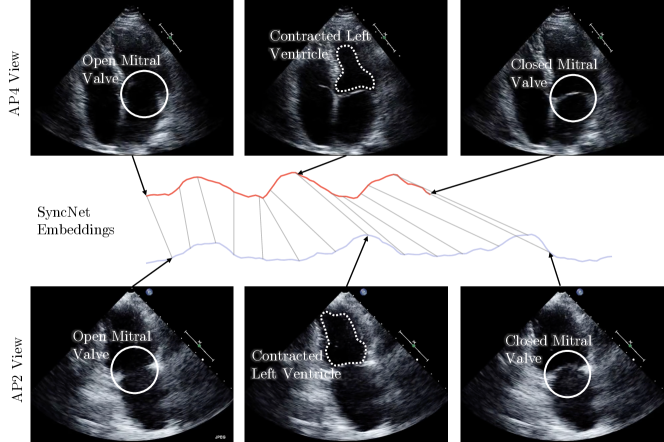

In Figure 6, the synchronization of an AP4 and AP2 echo cine is shown. To examine the details of the synchronization keyframes showing the max contraction of the left ventricle and the opening/closing of the mitral valve are shown. Additionally, we show the dynamic time warping correspondence between the embeddings of the two cines. Further information on the visualization of the cine embeddings in Figure 6 and the supplementary material is explained in Figure 7.

Refer to caption

Figure 6: A sample synchronization produced by Echo-SyncNet. We examine the synchronization of an AP4 and AP2 echo cine by comparing three distinct cardiac events: the earliest opening of the mitral valve, the maximum contraction of the left ventricle and the earliest closing of the mitral valve. We show the correspondence of these three cardiac events on the respective embeddings generated by Echo-SyncNet — AP4 (red), AP2 (blue). Additionally, a full mapping between the AP4 and AP2 embeddings is shown with thin gray lines. Please see the supplementary files for synchronized video results.

Figure 7: Visualization of embeddings: For each view, we show trajectories of the cines in the embedding space. Using a principal component analysis reduction approach, we reduce the dimensionality of the embedding from 128 to 1 for visualization. The visualization indicates how the embeddings change as the cardiac cycle progresses and how two cines with a different number of frames can be synced together. The images show a sample correspondence point (shown with black line in the lower sub-figure) for an AP4 and AP2 cardiac echo as well as their respective embeddings. Notice the corresponding position of the mitral valve in both images, and for a more obvious correspondence of cardiac walls and chambers during a cardiac cycle please see the supplementary videos.